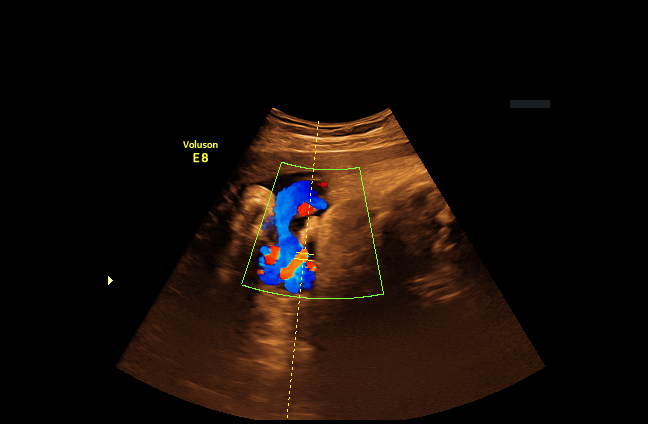

We begin with determining the direction of the ultrasound beam by utilizing the green Doppler box, which becomes active during color Doppler acquisition (see Fig. 3(a)). A binary mask of the green Doppler box is first obtained by color thresholding on the RGB pixels, followed by enhancing the mask using a watershed transform [6]. Next, a Hough line detection algorithm [1] is used to identify the two radial line segments on each side of the box. The ultrasound source is located at the intersection between the two line segments. As an extra step to prevent erroneous detection, we verify that we are able to detect the two arc lines with Hough circle detection when the center location is constrained to be at the intersection point from the previous two Hough lines (see Fig. 3(b)).

(a) Green Doppler box

(b) Detected line (red) and arc (blue)

Figure 3: Locating source of the ultrasound beam by using the green Doppler box.